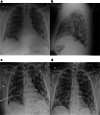

Methods: From 03/01/2020-03/20/2020, a retrospective review of all patients with suspected COVID-19 on imaging was performed. Imaging was interpreted by a board-certified, fellowship-trained radiologist. Patients were excluded if COVID-19 infection was suspected at the time of presentation, was the reason for imaging, or if any lower respiratory symptoms were present.

Results: Eight patients with suspected COVID-19 infection on imaging were encountered. Seven patients received testing due to suspicious imaging findings with subsequent lab-confirmed COVID-19. No patients endorsed prior exposure to COVID-19 or recent international travel. COVID-19 was suggested in six patients incidentally on abdominal CT and two on chest radiography. At the time of presentation, no patients were febrile, and seven endorsed gastrointestinal symptoms. Five COVID-19 patients eventually developed respiratory symptoms and required intubation. Two patients expired during the admission.